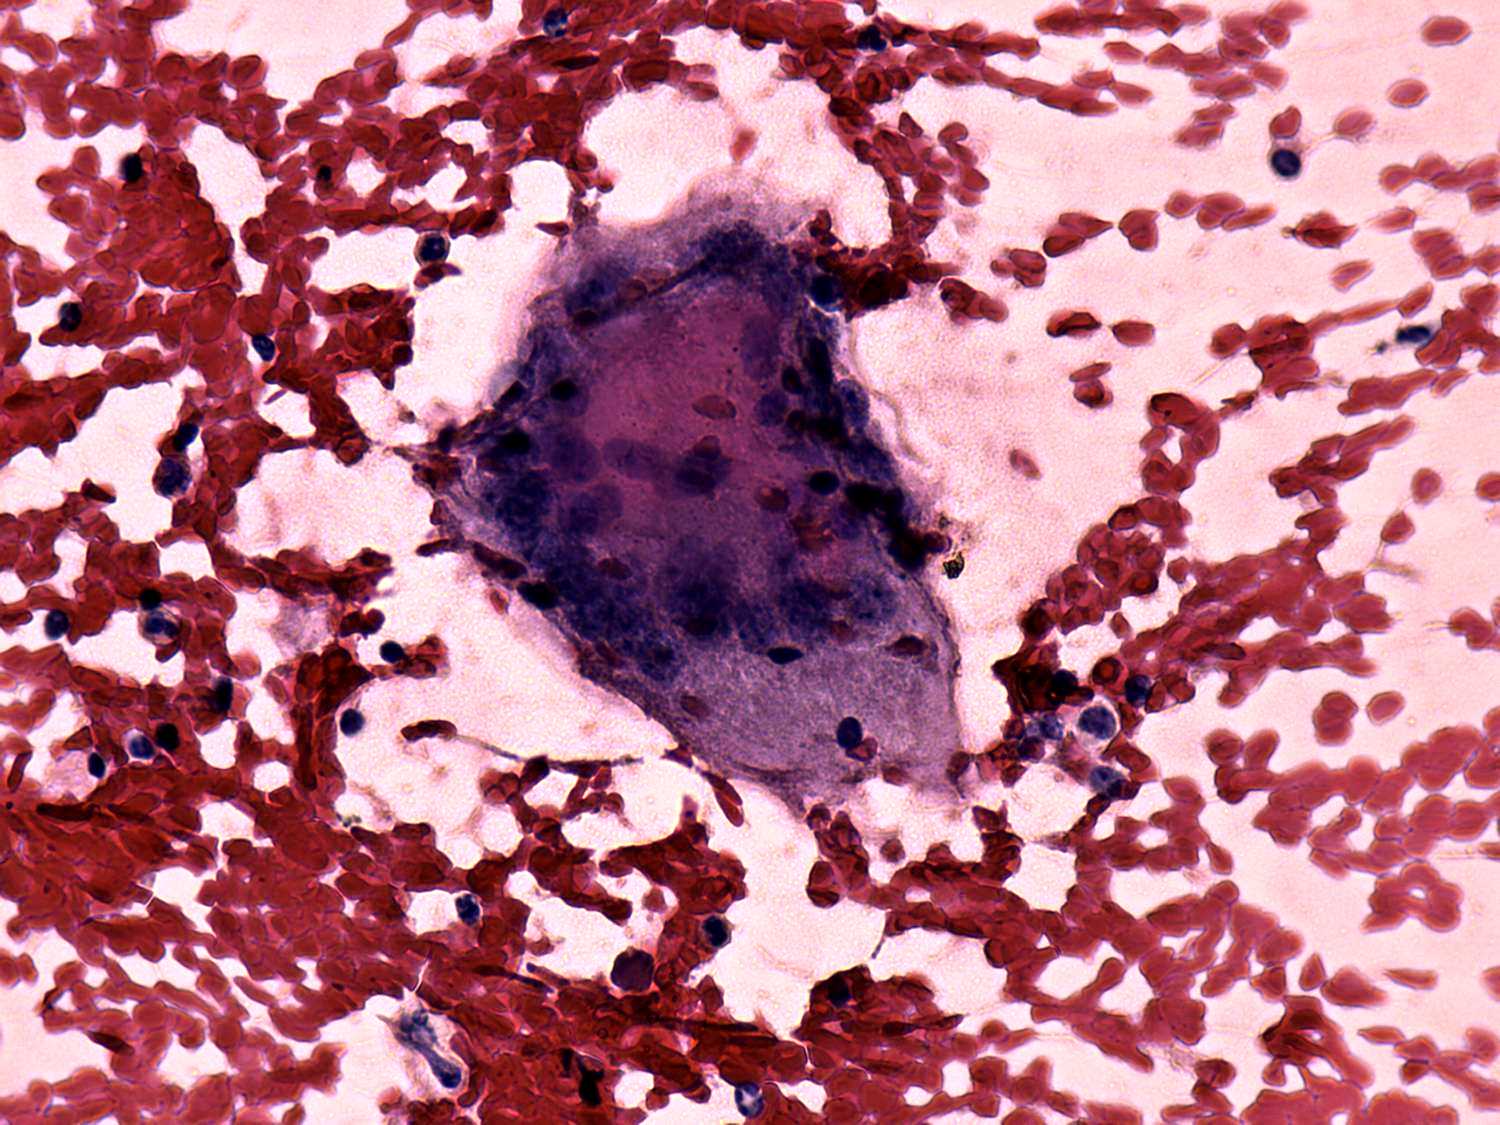

Cytological diagnosis: subacute, granulomatous de Quervain's thyroiditis.